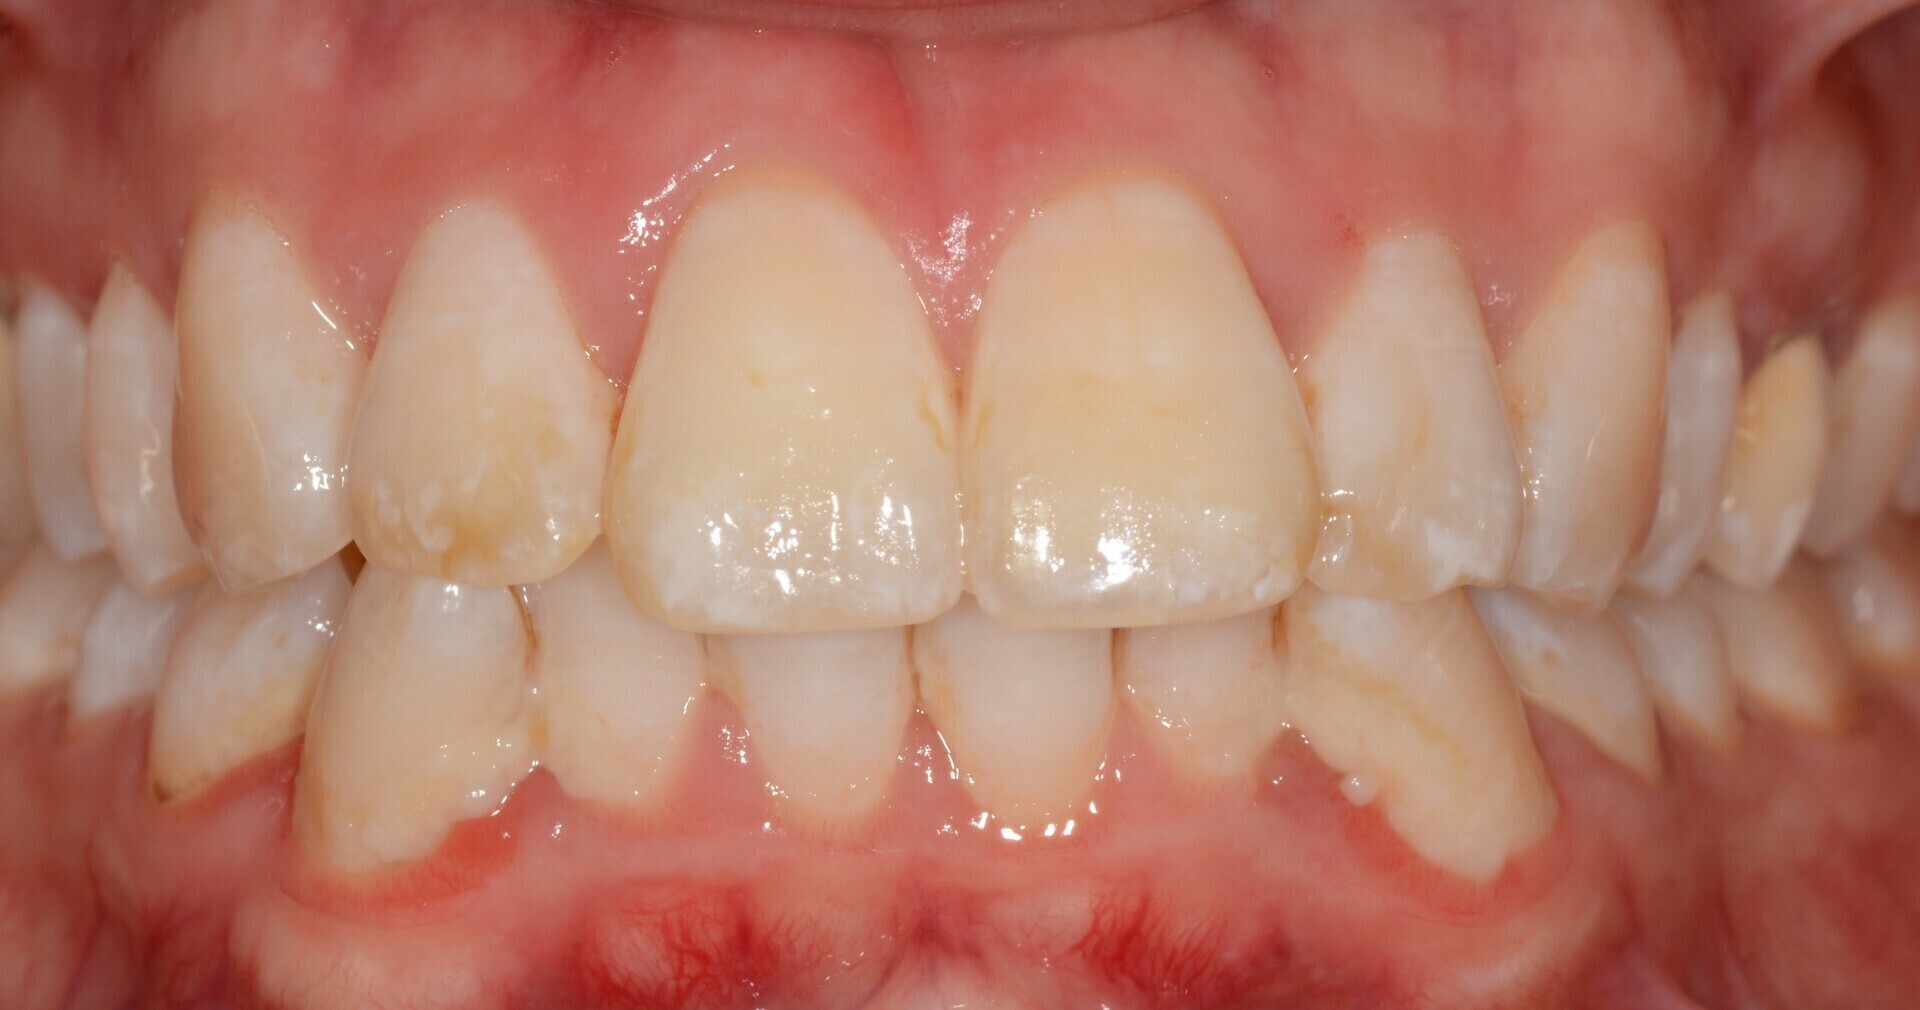

Le patient a 52 ans et il s’est usé les dents avec une brosse-à-dent très dure. Il a pensé bien faire en buvant beaucoup de jus de citron et en se faisant des bains-de-bouche à la chlorhéxidine. Nous sommes face à une abrasion d’origine mécanique et chimique et à des colorations dentaires d’origine médicamenteuse.

Des images photographiques en 2D et des images en 3D ont été couplées pour concevoir la réhabilitation du sourire et la proposer au patient.

L’occlusion (rencontre des dents) est optimisée.

Résultat final.

A l’aide d’un jeu de maquettes et d’usinage, les restaurations respectent le projet initial.